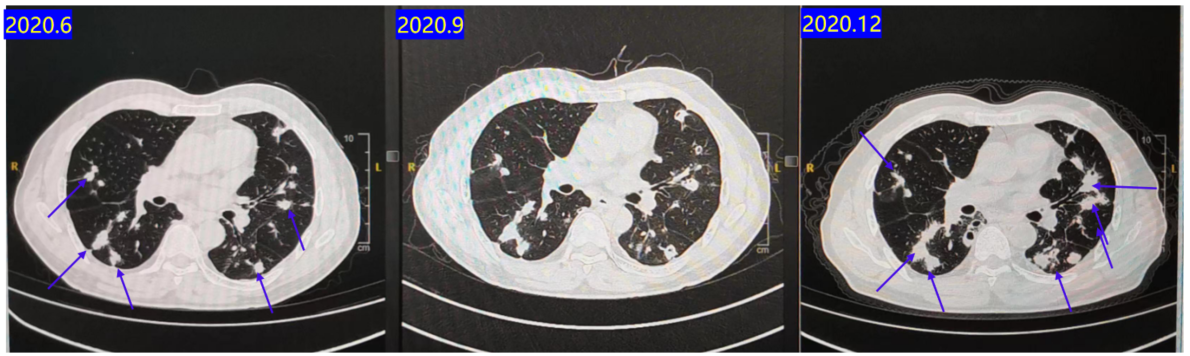

2016.07-2017.01:行XELOX方案辅助化疗6周期 + 卡培他滨2周期后停药。2018.07:复查CT提示新发肺部转移灶(图1)

2020.06-2020.12:行呋喹替尼靶向治疗。

疗效评估:C2评估SD,C4评估PD(图6)。PFS 6个月。